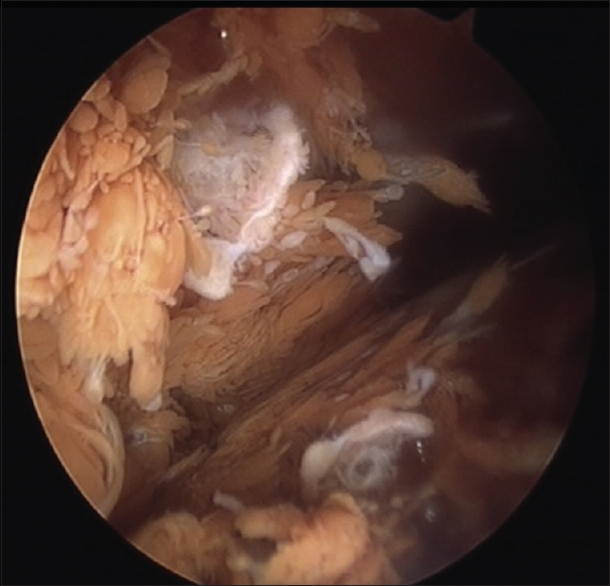

Bệnh nhân được lên lịch mổ nội soi khớp gối. Kết quả khi mổ là viêm bao hoạt dịch thể lông nốt sắc tố (PVNS, Pigmented Villonodular Synovitis), được phẫu thuật viên cắt bỏ các phần u nhú của bao hoạt dịch.

Trong Viêm màng hoạt dịch thể lông nốt sắc tố, dịch khớp màu hồng, dịch máu không đông và sinh thiết màng hoạt dịch có lắng đọng sắc tố hemosiderin và tế bào khổng lồ đa nhân.

Trên hình ảnh cộng hưởng từ PVNS được xác định bởi nhiều khối mô mềm trong khớp, có thuỳ. Các tổn thương có cường độ tín hiệu trung bình đến thấp trên cả T1 và T2. Các tổn thương PVNS rất dễ chảy máu, dẫn đến lắng đọng đặc trưng của hemosiderin có cường độ tín hiệu rất thấp. Ngoài ra, cộng hưởng từ còn xác định rõ sự ăn mòn vào xương hoặc mô mềm kế cận như gân bánh chè.